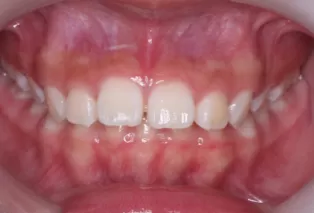

Photos intra-orales après traitement